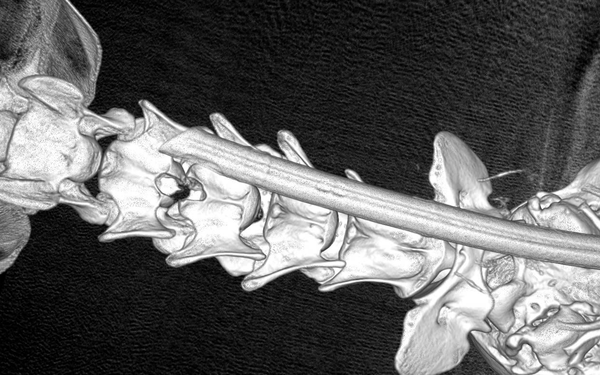

CT-scan thú y cho thấy đĩa đệm C4 – C5 thoát vịchèn ép tủy sống cổ, gây ra các biểu hiện thần kinh rõ rệt.

• CT- scan: Xác định đĩa đệm C4 – C5 thoát vị, chèn ép lên tủy sống cổ, gây ra triệu chứng thần kinh.

Hình ảnh CT thể hiện đĩa đệm cổ bị phồng ra phía sau, làm biến dạng tủy sống. Ngoài ra, các đĩa đệm lân cận cũng có dấu hiệu thoái hóa — cho thấy bệnh thoát vị đĩa đệm tiến triển mạn tính.